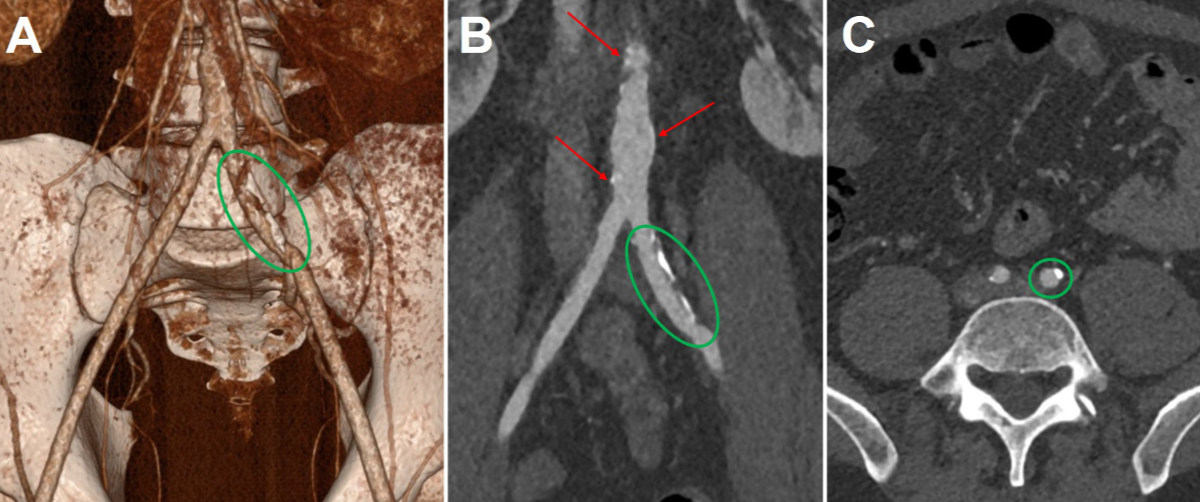

A 42-year-old man with homozygous familial hypercholesterolaemia and a confirmed homozygous LDLR mutation experienced significant progression of his atherosclerotic cardiovascular disease over the years, despite receiving maximum lipid-lowering therapy. At the age of 11 years, he underwent his first percutaneous coronary intervention (PCI) for a high-grade stenosis of the left main coronary artery. Since then, he has been treated with high-intensity statins, ezetimibe and weekly apheresis. In 2021, aged 39, he underwent triple coronary bypass surgery and replacement of the ascending aorta because of progressive coronary artery disease (figure 1) and a highly calcified aortic root. Two years later, in 2023, he experienced a myocardial infarction caused by an acute occlusion of the right coronary artery (saphenous vein graft chronically occluded). Simultaneously, a computed tomography angiography scan demonstrated diffuse peripheral arterial occlusive disease with atheromatous infiltration in the ilio-femoral region (figure 2) as well as bilateral atheromatous infiltration of the carotids, indicating systemic polyvascular atherosclerotic infiltration.

Figure 2Computed tomography angiography. 3D reconstruction (A), coronal view (B) and axial view (C) demonstrating atheromatous infiltration in the descending aorta (red arrows) and in the two common iliac arteries (green circles) in 2023 (age 40 years).